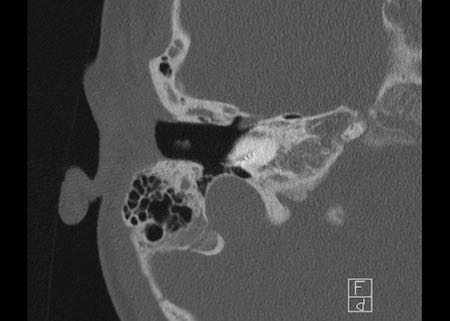

Cholesteatoma

Cholesteatoma: Phụ nữ 20 tuổi với viêm tai tái phát. Mô hạt trên màng nhĩ trái. Khối mô mềm nằm giữa chuỗi xương con và thành nhĩ bên, có hình ảnh bị ăn mòn. Bên phải để so sánh.

Cholesteatoma được cho là xuất phát từ các túi co kéo của màng nhĩ.

Tổn thương dần dần phát triển theo thời gian do quá trình bong vảy và bao bọc mô.

Hầu hết các cholesteatoma là mắc phải, nhưng một số là bẩm sinh.

Các bác sĩ phẫu thuật Tai Mũi Họng thường cho rằng cholesteatoma là một chẩn đoán lâm sàng.

Các mảnh cholesteatoma có thể nhìn thấy trong ống tai ngoài.

Trên CT, cholesteatoma nhỏ biểu hiện là một khối mô mềm.

Trong giai đoạn bệnh tiến triển hơn, có thể xuất hiện các vùng ăn mòn xương.

Cholesteatoma lớn có thể ăn mòn các xương con và thành hòm nhĩ, đồng thời lan rộng vào hố sọ giữa.

Bên trái là hình ảnh của một phụ nữ 20 tuổi với viêm tai tái phát.

Có mô hạt trên màng nhĩ trái.

CT cho thấy một khối mô mềm nằm giữa chuỗi xương con và thành nhĩ bên, có hình ảnh bị ăn mòn.

Điều này ủng hộ chẩn đoán cholesteatoma.